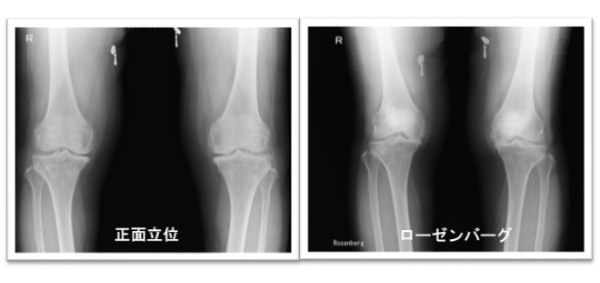

変形性膝関節症

変形性膝関節症とは、簡単にいえば、自動車のタイヤが減るように、長年の負担で膝関節の軟骨がすりへった状態をいいます。ですから、変形性膝関節症は純粋に病気とはいえず、年をとれば大なり小なり誰にでも起こってくる状態ともいえます。ただし、年をとれば全員に膝関節の痛みが出てくるわけではありません。